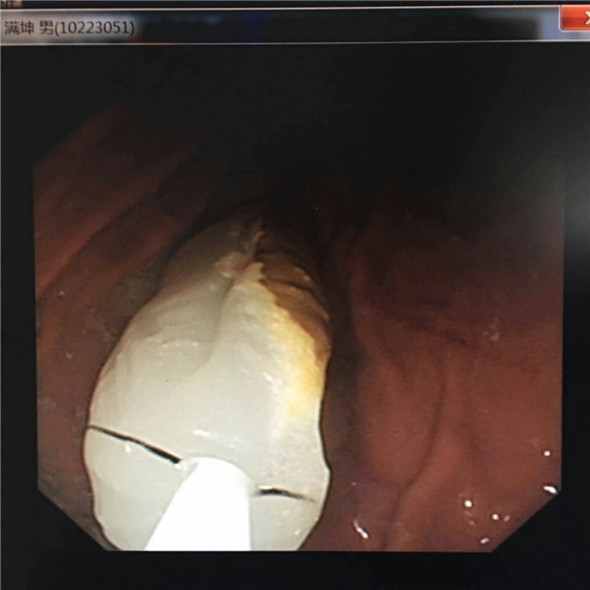

第二天一早,腔镜室就已经准备妥当,等待这位患者了,由王明涛主任为患者进行手术,这个手术的难点在于这块梭型玉石长约6Cm,表面光滑,重量较重。所以在取出时可能面临两个问题,一个是玉石大,表面光滑不易抓住;二是在取出过程中容易卡在食道的狭窄处,造成患者窒息。

在手术的开始王主任尝试用异物钳取物,但是玉石太光滑很难抓住,后改用圈套器,试了几次石块都会从钢丝内脱落。30分钟的时间过去,患者已经开始躁动不安了。王主任冷静应对用石网篮取石,网蓝的四线钢丝应该比两线的圈套器抓取的更牢固,经过尝试果然见效,石块抓住了,但也只是抓住了石块尾部很难完整拖出,遂即又向食道内下滑管,不断旋镜调整角度,最后,借助滑管的扩张力将玉石取出。一般来说胃镜取物术只需要20分钟,但是这次手术却花费了一个小时,主治医生的脸上早就布满汗水,护士的手腕也被患者握出紫痕。好在经过手术,患者已经可以安然出院了。

男子所吞6cm长玉坠